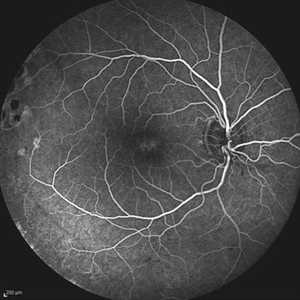

Behcet's Disease Behcet's DiseaseMar 13 2013 by Hamid Ahmadieh, MD Late phase FA of the left eye of a 23-year-old man with retinal vasculitis due to Behcet's disease . Photographer: Solmaz Shahmohammad, Negah Eye Center, Tehran Imaging device: Heidelberg Spectralis Condition/keywords: retinal vasculitis

Behcet's Disease Behcet's DiseaseMar 13 2013 by Hamid Ahmadieh, MD Wide field FA of the left eye of a 23-year-old man with retinal vasculitis due to Behcet's disease . Photographer: Solmaz Shahmohammadi , Negah Eye Center, Tehran Imaging device: Heidelberg Spectralis Condition/keywords: retinal vasculitis